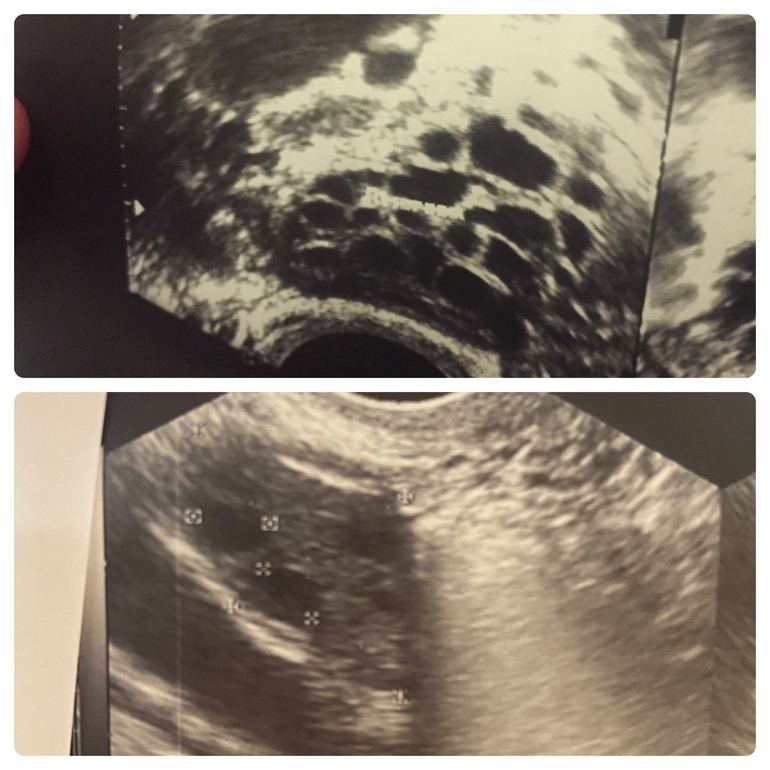

Имеет смысл при СПКЯ, я пробовала пить фертину - без результата, перешла на мио инозитол с айхерба, овуляция стала происходить раньше и яичники стали выглядеть намного лучше. Вот так было у меня до приёма и во время, сверху - до, снизу - во время. Пью весь цикл без перерыва по 2000.